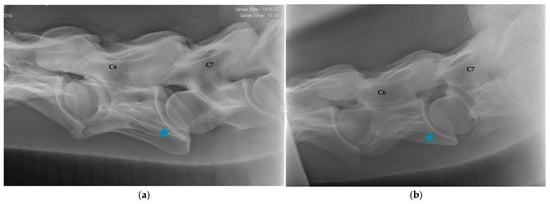

2.1.2. Radiographic Assessment

- Group 1 = normal: no periarticular new bone formation at ventral margins of APJ, intervertebral foramina clearly visible.

- Group 2 = mild APM: minimal/equivocal enlargement and sclerosis of APJ with mild osteophytosis ventrally, intervertebral foramina open/slightly obscured by new bone formation.

- Group 3 = moderate/severe APM: clear enlargement and sclerosis of APJ with moderate osteophytosis ventrally, significant reduction/loss of intervertebral foramina.